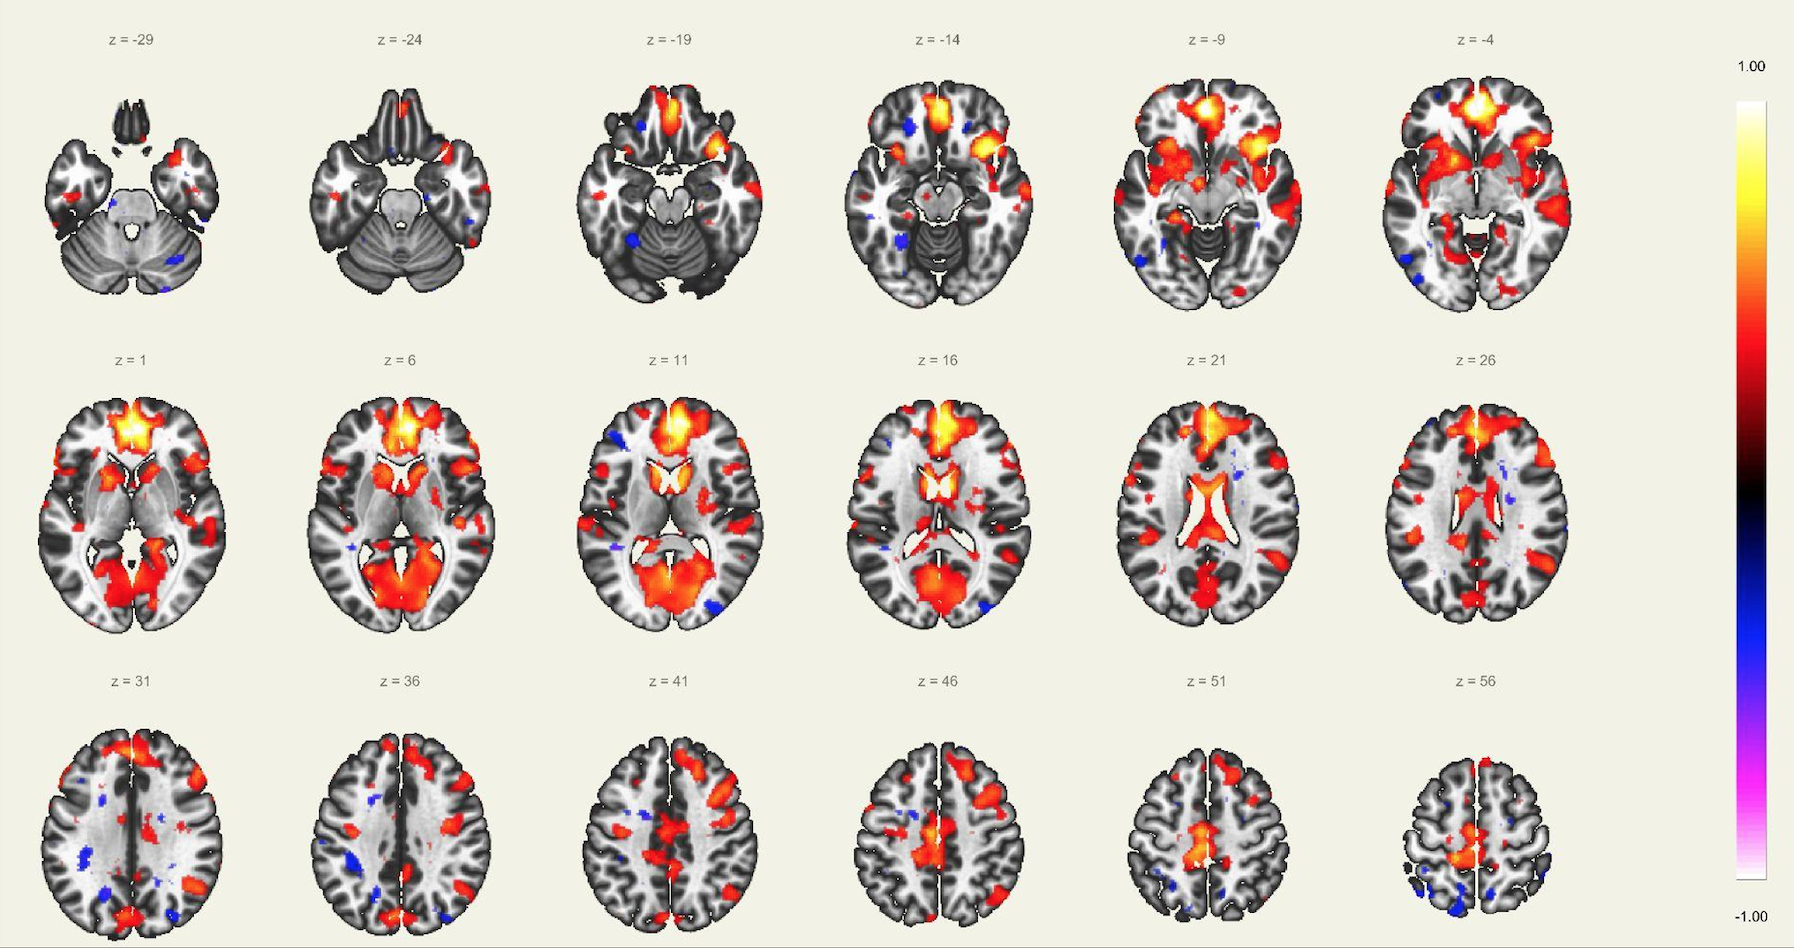

En este estudio, el escaneo se realizó con un resonador de 3 Tesla del servicio de diagnóstico por imágenes de la Clínica Internacional, a un paciente joven, sin comorbilidades ni antecedentes de importancia, el cual estuvo despierto en todo momento y con los ojos cerrados. Además, se le dio instrucciones de completar palabras mentalmente sin emitir sonido alguno o hacer gestos, llegando a identificarse las distintas redes cerebrales detalladas posteriormente.

El estudio fue realizado con secuencia BOLD, con los siguientes parámetros: cortes: 40, factor de distancia: 0%, Field of View: 240 mm, grosor de corte: 4 mm, tamaño de vóxel: 3.8 x 3.8 x 4 mm, TR: 3000 ms, TE: 30 ms, Umbral: 4 y tamaño del paradigma 20.

DISTINTAS CONEXIONES CEREBRALES EN ESTADO DE REPOSO

A pesar de la ausencia actividad física, resulta imposible indicar que no se esté realizando ningún tipo de actividad mental, como recuerdos o el uso de la imaginación. La consecuencia de esto se ve reflejada en los cambios de la actividad neuronal.16 A través de este método de vóxel semilla se ha logrado identificar distintas redes de conectividad funcional descritos a continuación: